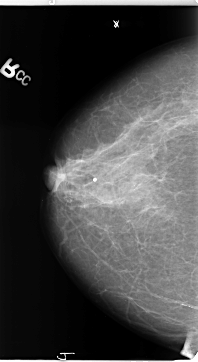

B_3137_1.LEFT_CC

LEFT_CC LINES 4704 PIXELS_PER_LINE 2496 BITS_PER_PIXEL 12 RESOLUTION 50 NON_OVERLAY